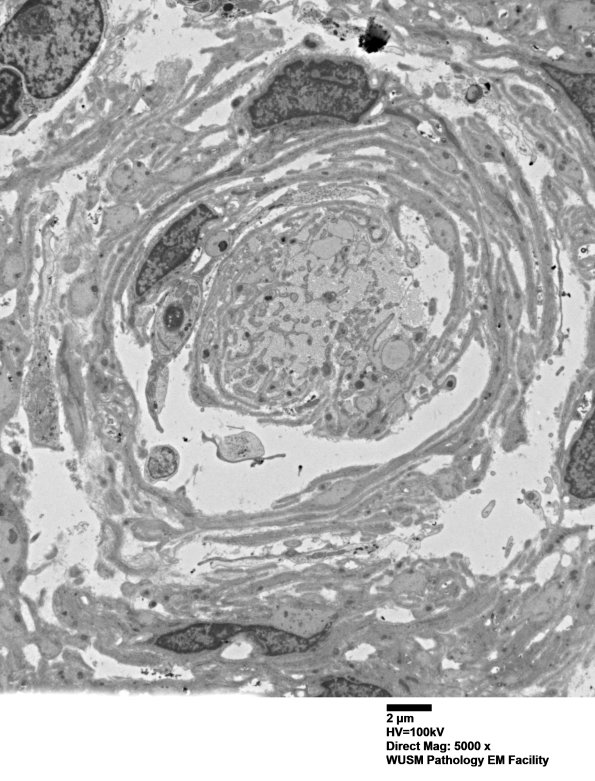

Washington University Experience | PERIPHERAL NEUROPATHY | 20 PSEUDO-ONION BULBS | 8C1B (Case 8) Nerve_013 - Copy

8C1B-E Progressively higher magnification of image# 8C1A. (electron micrographs)